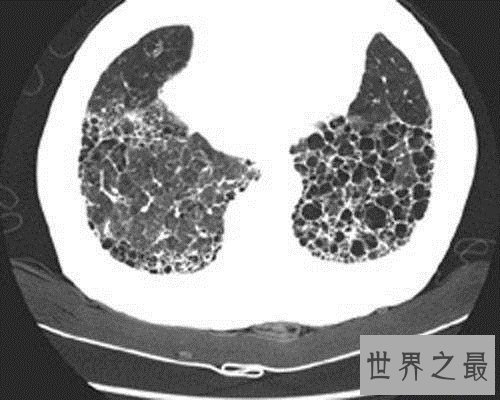

患者在病情重大者会出现气喘,全身乏力,体重减轻,心慌出虚汗,杵状指及唇甲紫绀。血常规反省,发现细菌感染时,中性粒细胞增高,白细胞计数多显著增高,若为病毒感染时,白细胞多失常或低下。X线反省反省发现两肺纹理增重,沿支气管散布散在小片状或点状浸润暗影。

另外,停止性呼吸艰巨为本病特色,刺激性干咳或伴大批粘痰,多数有黄痰及血痰,乏力、消瘦、关节疼痛、低热等,肺底及腋下区可闻及爆裂性罗音,吸气末听到,表浅毛糙、调高,可有肺气肿及右心衰竭等。